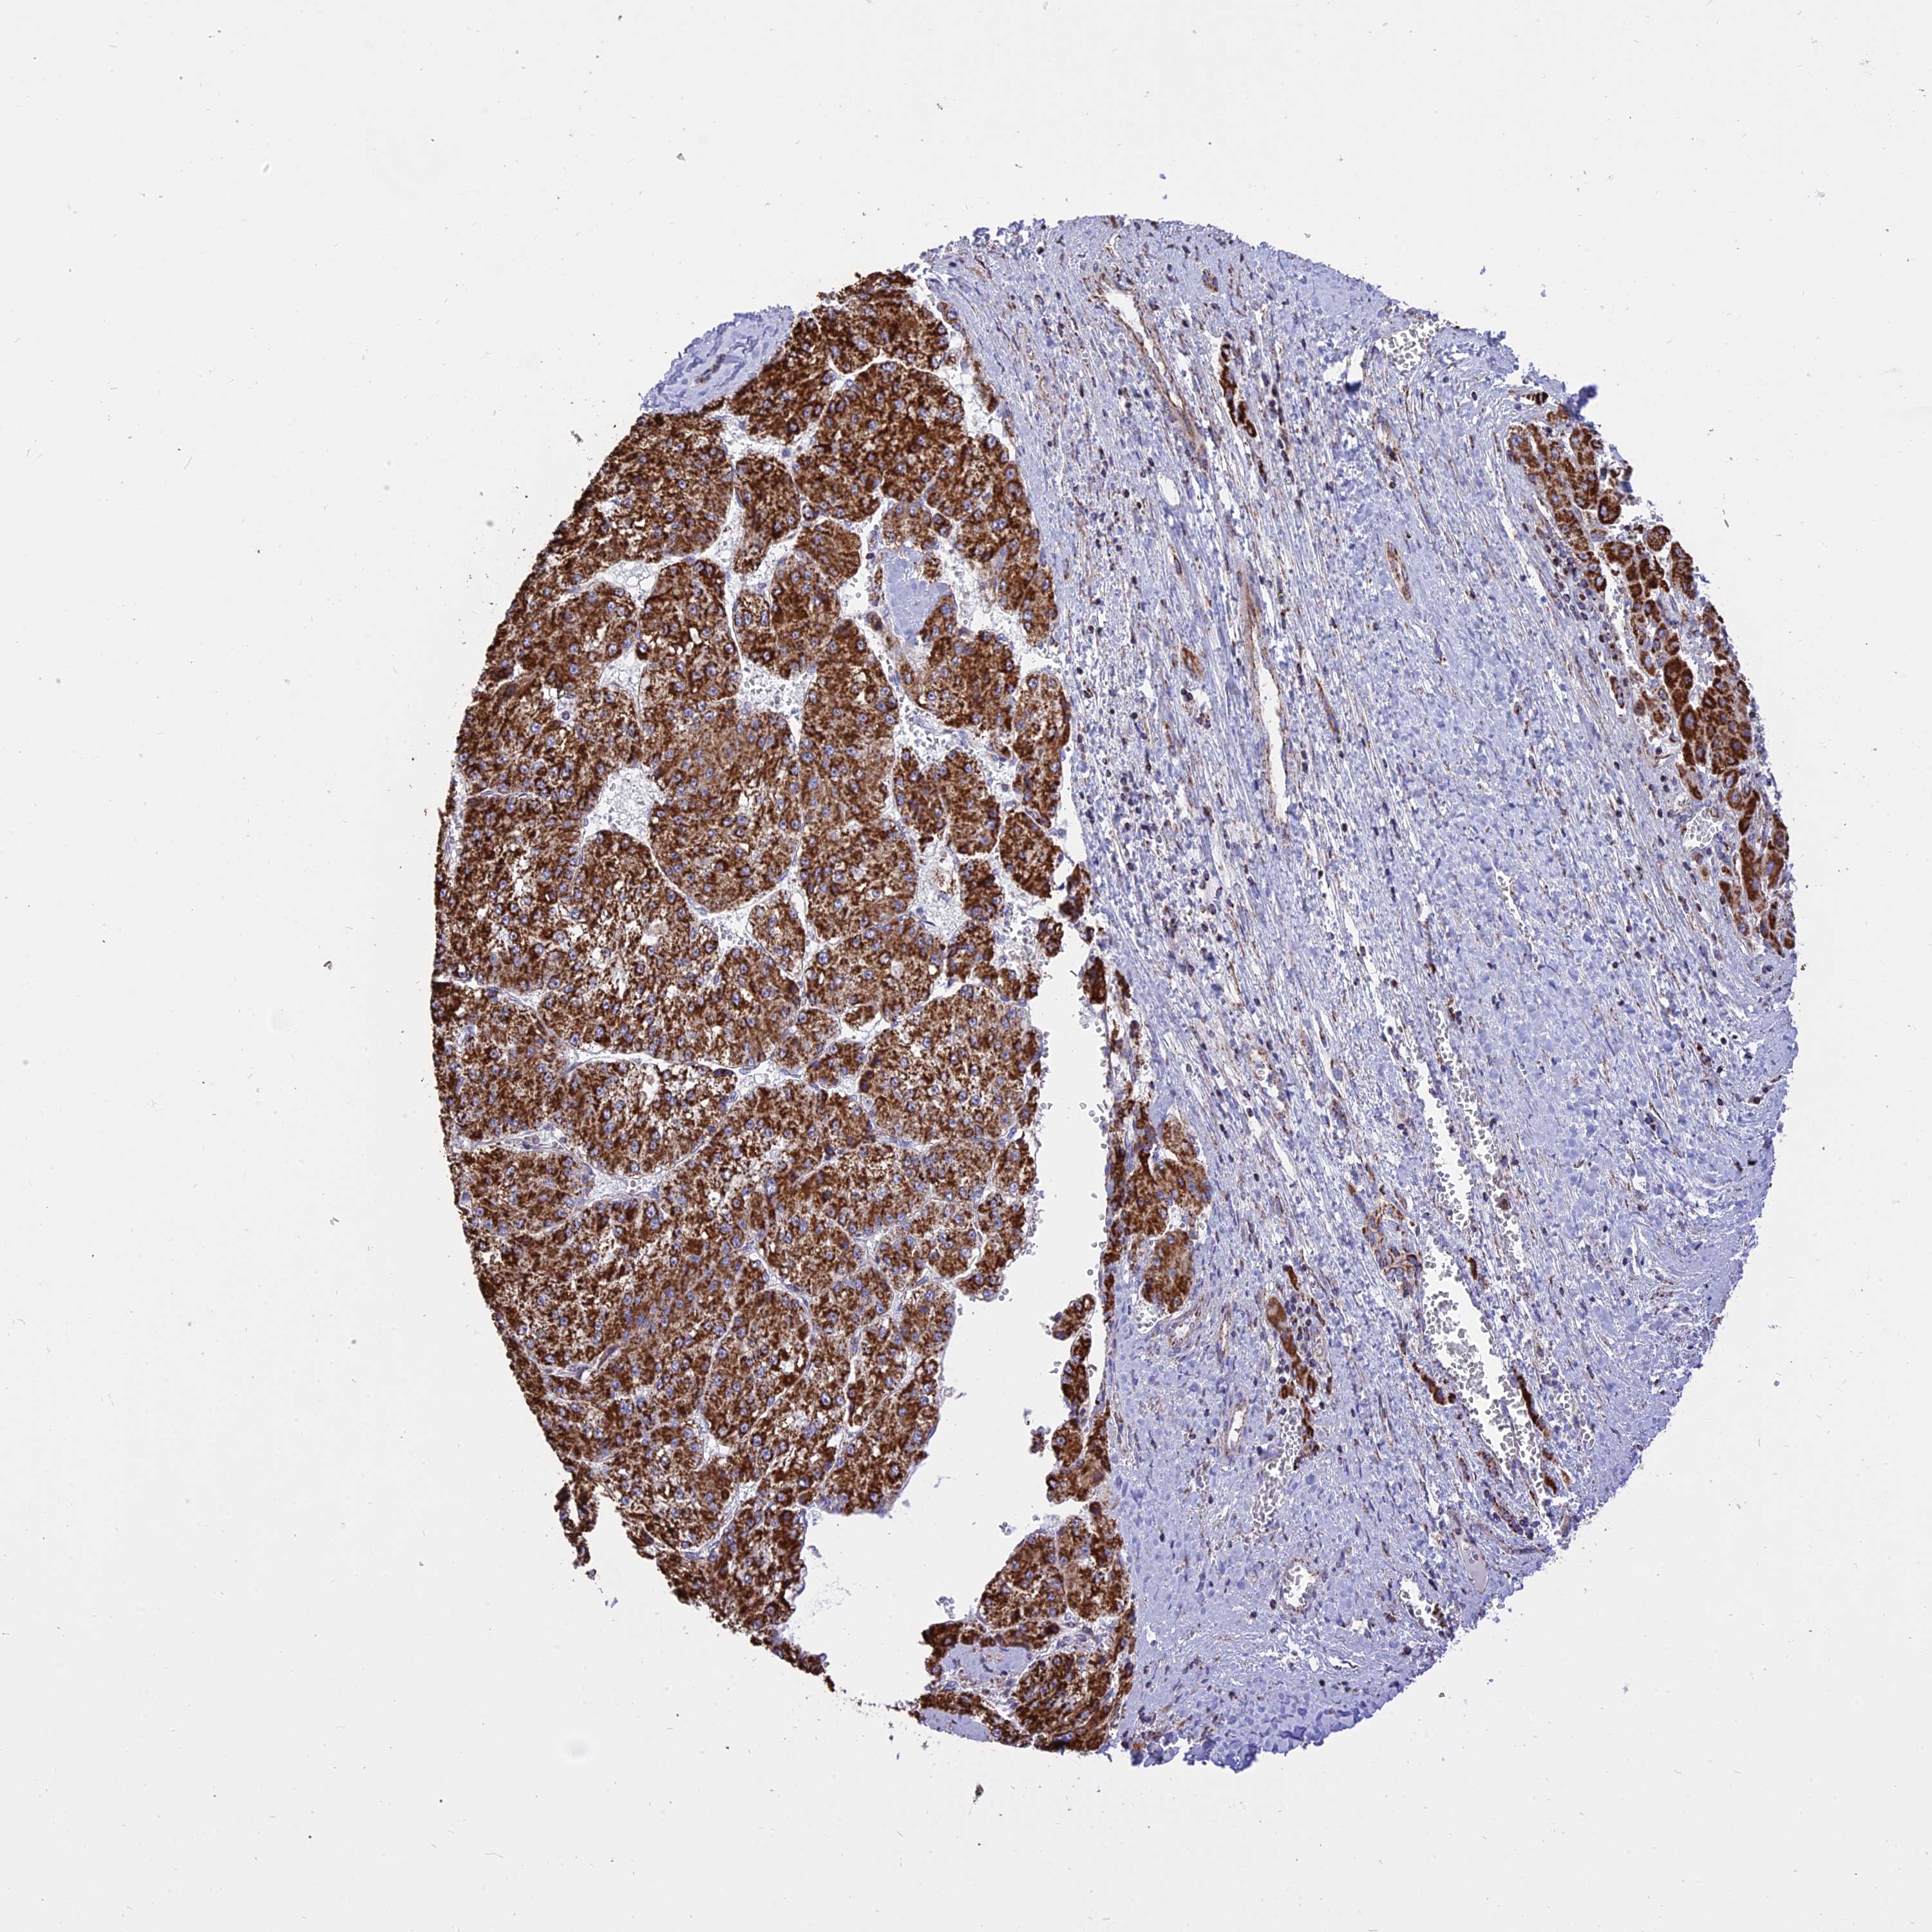

LIVER CANCER - Protein expressioni

A mouse-over function shows sample information and annotation data. Click on an image to view it in a full screen mode. Samples can be filtered based on level of antibody staining by selecting one or several of the following categories: high, medium, low and not detected. The assay and annotation is described here.

Note that samples used for immunohistochemistry by the Human Protein Atlas do not correspond to samples in the TCGA dataset.

Antibody stainingi

Antibody staining in the annotated cell types in the current human tissue is reported as not detected, low, medium, or high, based on conventional immunohistochemistry profiling in selected tissues. This score is based on the combination of the staining intensity and fraction of stained cells.

Each image is clickable and will lead to virtual microscopy that enables deeper exploration of all samples and also displays staining intensity scores, fraction scores and subcellular localization as well as patient and tissue information for each sample.

Antibody HPA041608

Antibody HPA042459

Staining

High

Medium

Low

Not detected

Intensity

Strong

Moderate

Weak

Negative

Quantity

>75%

75%-25%

<25%

None

Location

Nuclear

Cytoplasmic/membranous

Cytoplasmic/membranous,nuclear

Cholangiocarcinoma

Carcinoma, Hepatocellular, NOS